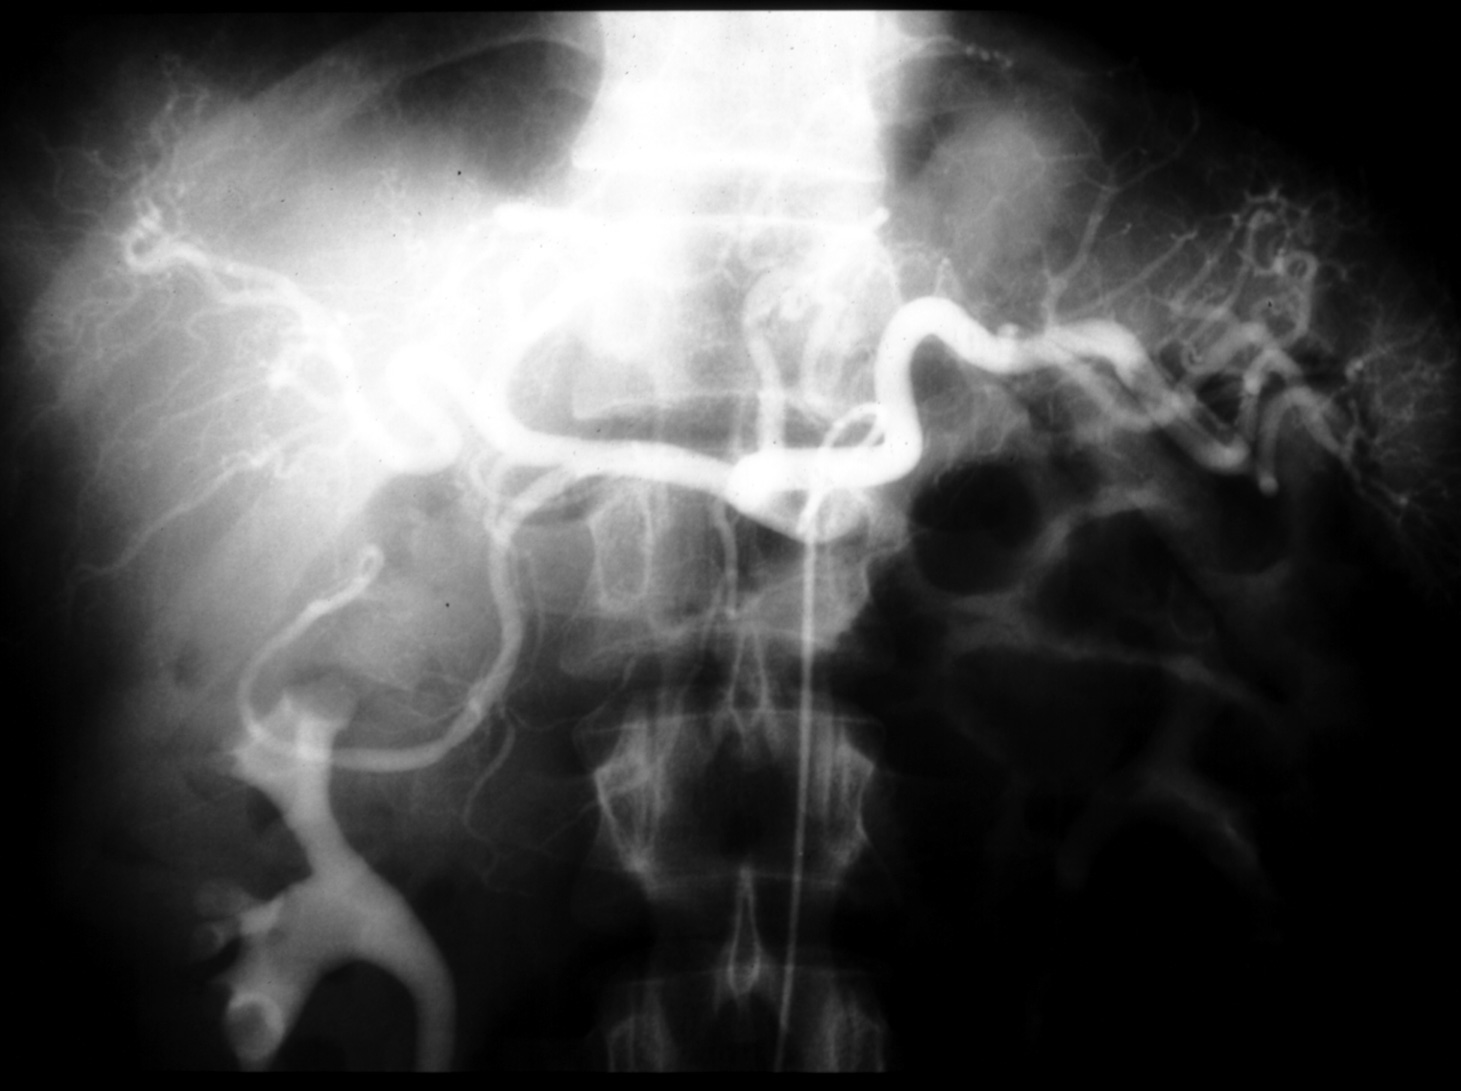

MS I ??? - Celiac Arteriogram (Arterial Phase)

Identify: main hepatic, splenic left gastric, hepatic proper, gastroduodenal,

right and left hapatic arteries